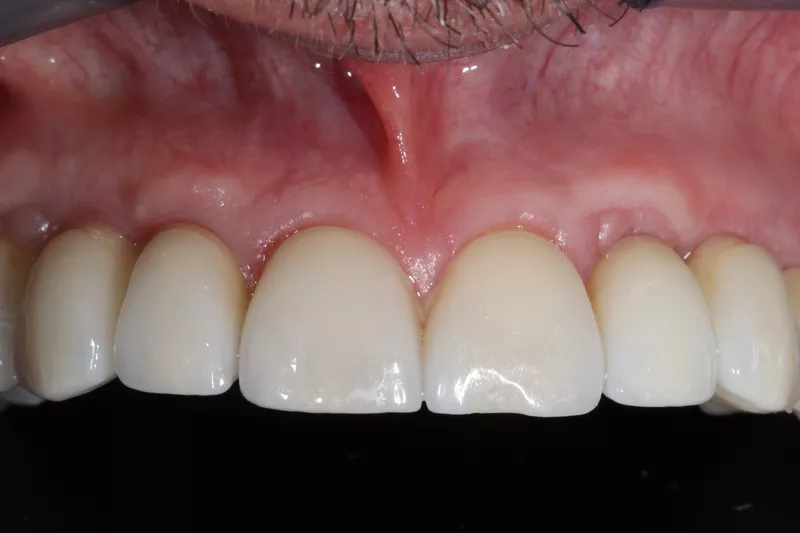

16a-b. Final situation after inserting bridges to 15 Ncm, cementing the crown to tooth 15, and gluing the veneers to teeth 11 and 21.

16c. 4 years post implant placement.

18. Situation 4 years post implant placement.